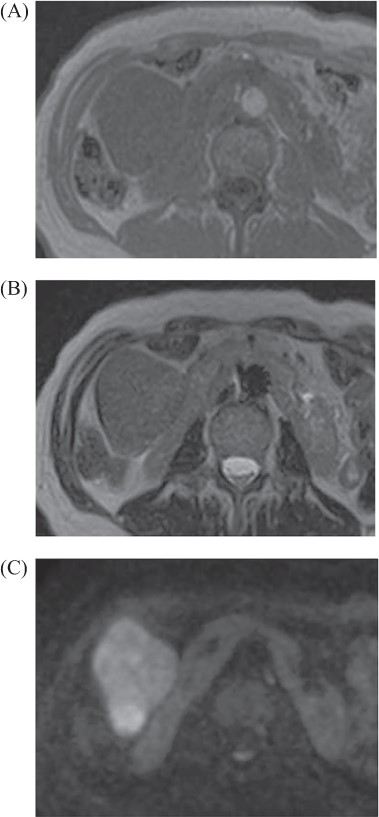

A 69-year-old woman presented to our institution with right abdominal pain. There was nothing special to mention in her family history. Her past medical history included horseshoe kidney, gastric ulcer, and asthma. Physical examination revealed a slight tenderness of the right quadrant abdomen. All laboratory parameters including the tumor markers carcinoembryonic antigen and carbohydrate antigen 19-9 were within normal limits. Abdominal ultrasonography showed a regularly shaped uniform tumor of about 50 mm in diameter that was located in the right retroperitoneum ventral to the right part of the horseshoe kidney. The tumor was hypervascularized (Fig. 1). Computed tomography (CT) showed a tumor of 80 mm in diameter ventral to the right part of the horseshoe kidney and the dorsal side of the descending part of the duodenum. On contrast-enhanced CT, the tumor showed late-phase enhancement. There were no findings of invasion into any organs and right ovarian vein ran through the tumor (Fig. 2). No metastases to organs or swollen lymph nodes were found. Magnetic resonance imaging (MRI) showed a tumor that was isointense with respect to muscle on T1-weighted images and of high-signal intensity on T2-weighted images (Fig. 3). No fatty components were detected in the tumor. Endoscopic ultrasonography showed a regularly shaped and hypoechoic tumor with no connection to the right part of the horseshoe kidney or duodenum (Fig. 4). Our working diagnosis was a retroperitoneal tumor that could be either a malignant lymphoma, leiomyoma or gastrointestinal stromal tumor.

Abdominal MRI: tumor revealed iso intensity with muscle in T1 weighted image (A), slightly high intensity in T2 weighted image (B) and abnormal signal in diffuse weighted image (C).